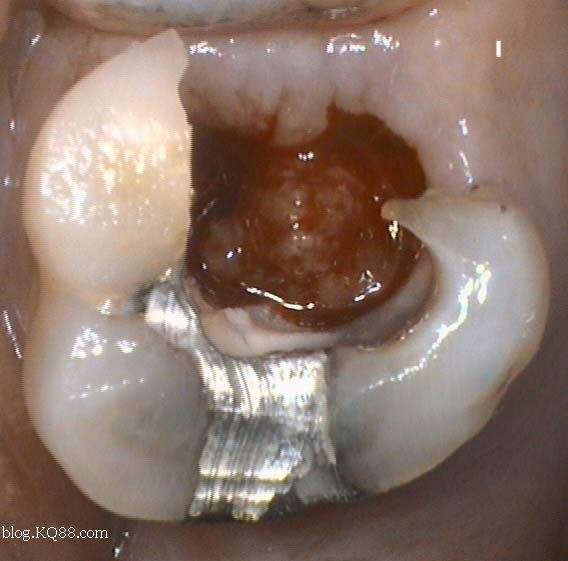

口腔檢查

1、口腔鏡檢查:通過口腔鏡檢查,可以清晰地觀察到牙齒表面的牙洞以及牙洞內(nèi)的情況,醫(yī)生可以判斷牙洞是否已深入牙髓,并評估病情嚴重程度。

2、探診檢查:使用牙科探針檢查牙洞周圍組織的健康狀況,了解牙洞深度及與牙髓的關(guān)系。

根據(jù)以上觀察、口腔檢查和X光檢查結(jié)果,醫(yī)生將綜合判斷牙齒牙洞是否已深入牙髓,如果牙洞較淺,未涉及牙髓,可以通過補牙等方式進行治療;如果牙洞已深入牙髓,可能需要進行根管治療等更復(fù)雜的治療措施。